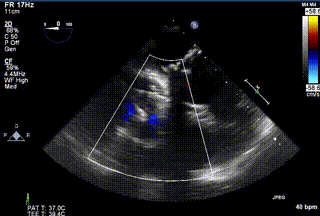

2021年12月24日,復(fù)旦大學(xué)附屬中山醫(yī)院葛均波院士團隊成功應(yīng)用LuX-Valve Plus為一例極重度三尖瓣反流(TR)合并房顫、房缺的患者完成了經(jīng)血管三尖瓣置換術(shù),這是在前基礎(chǔ)上,本周完成的第三例經(jīng)血管三尖瓣置換手術(shù),葛均波院士、周達(dá)新教授等與心外科魏來教授、賴顥教授,心超室的潘翠珍教授、李偉教授及麻醉科的郭克芳教授共同完成了本周手術(shù),均獲得圓滿成功!患者術(shù)后超聲顯示無TR,臨床癥狀明顯改善。本周手術(shù)的成功也為LuX-Valve Plus救治性臨床研究添上了濃墨重彩的一筆。

三例患者入院后,葛均波院士團隊周達(dá)新教授、潘文志教授、張源博士、陳莎莎博士及心超室的潘翠珍教授、李偉教授對患者的情況進(jìn)行詳細(xì)評估和討論,最終決定為三例患者選擇LuX-Valve Plus40mm、50mm和50mm型號的瓣膜進(jìn)行手術(shù)治療。手術(shù)后即刻拔除氣管插管,術(shù)后患者三尖瓣反流癥狀得到顯著改善,復(fù)查心超結(jié)果顯示人工三尖瓣瓣膜支架固定穩(wěn)定,瓣葉關(guān)閉形態(tài)未見異常,未見明顯反流。